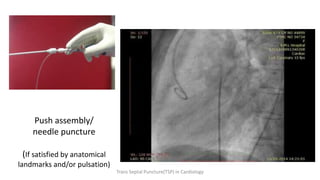

6. Confirm in LAO: needle should be directed posterior.

7. Advance needle into LA. Confirm by pressure, LA injection of

contrast by fluoroscopy.

8. Advance sheath/dilator into LA. Careful about tenting septum and not

pushing needle too far into LA.

9. Remove dilator and needle.

Transseptal Procedure Steps

Push assembly/

needle puncture

(If satisfied by anatomical

landmarks and/or pulsation)